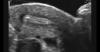

А когда мне развернули монитор узи аппарата и показали эту маленькую бусинку со словами - «вот посмотрите, это матка,а маленькое белое пятнышко в ней ваш малыш», то разрыдалась в три ручья😁

Надеюсь с помощью Всевышнего малыш останется со мной на долгие 9 месяцев🤲🏻🤲🏻❤️